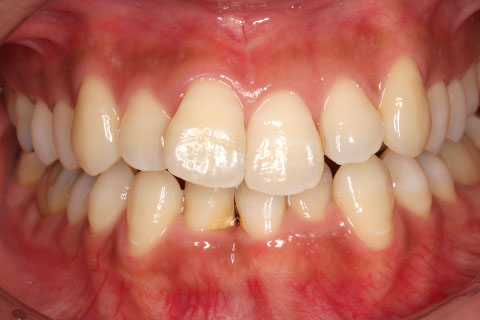

ハーフリンガル矯正3:上の歯のみ舌側矯正で治療(矯正期間24ヶ月)

治療前

治療中(開始直後)

治療中(開始半年後)

治療後

- 年齢・性別

- 25歳女性

- 治療期間

- 2年0ヶ月

- 抜歯

- 上下4番抜歯

- 治療費

- 110万円

- 治療内容

- 施術の副作用(リスク)

- 表側矯正と比較して、力学的な操作性が複雑なため、ボーイングエフェクトを起こしやすい。